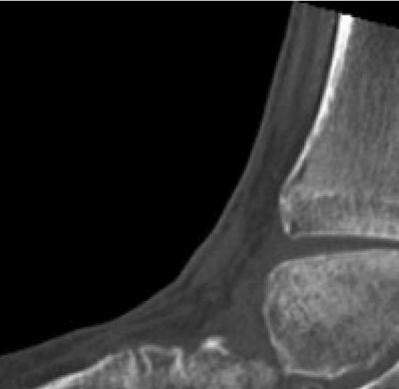

921 Charcot Neuroarthropathy of the Foot and Ankle in the Acute Setting: An Illustrative Case Report and Targeted Review

Kian Bagheri, Albert T. Anastasio, Alexandra Krez, Lauren Siewny, Samuel B. Adams